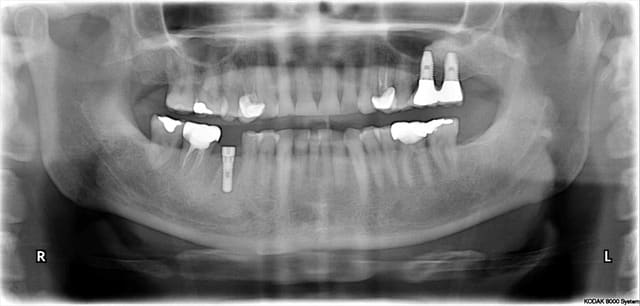

Implant wq5dd1 - Eugenol

sinuslift

06/05/2010 à 15h11

juste pour rire un des cas de ce matin, patient arrivant de la capitale très surpris pas mes tarifs!

sinus lift fait il y a environ 2 ans à paris,posé par un très bon, du nobel sans doute

Pourtant, Je parie sur ma sous m....